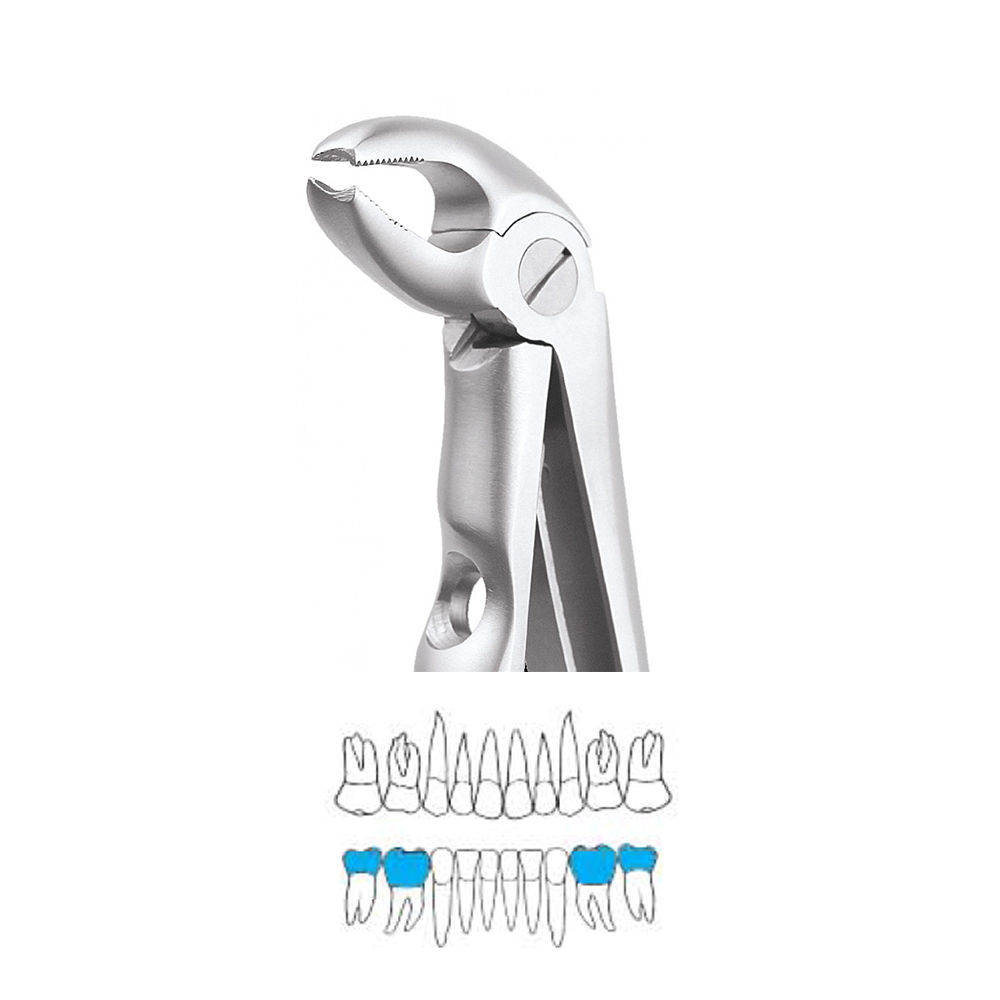

Pedo Extraction Forceps: These specialized forceps are designed to extract deciduous (baby) teeth gently. They have smaller, anatomically adapted beaks that fit comfortably around the smaller roots of baby teeth, reducing the risk of trauma during extraction. The handles are designed for easy grip and better control, ensuring a safe and efficient extraction process.

Pedo American Forceps: These forceps are designed to grip and extract deciduous teeth that are mobile or need removal. They have unique beak designs that cater to the varying shapes and sizes of baby teeth, providing a secure hold for extraction while minimizing any discomfort for the child.